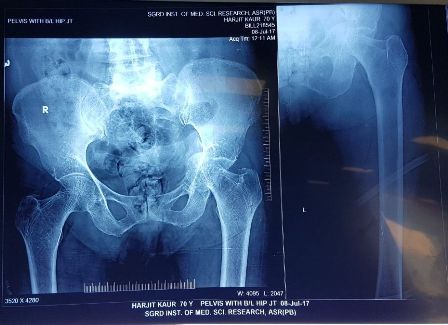

Patient : Mrs. Harjit Kaur

Age / Sex : 70 yrs Female

Procedure : THR (Total Hip Replacement) left side done

• A case of neglected fracture.

• Fracture dislocation of Hip joint.

• Plan (THR) Total HIP Replacement while Acetabulum Exposure there is no wall on superior and posterior aspect, Central Wall also absent.

• Having no option, decided to put cage in the Acetabulum and done cemented Total Hip Replacement.

• Now patient is ambulatory without any aid.